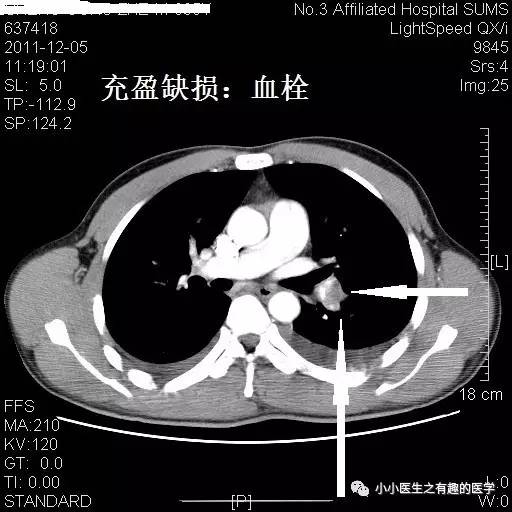

再来一例。我读研究生期间的病人。

小小的充盈缺损。

看小小血栓,也不难。